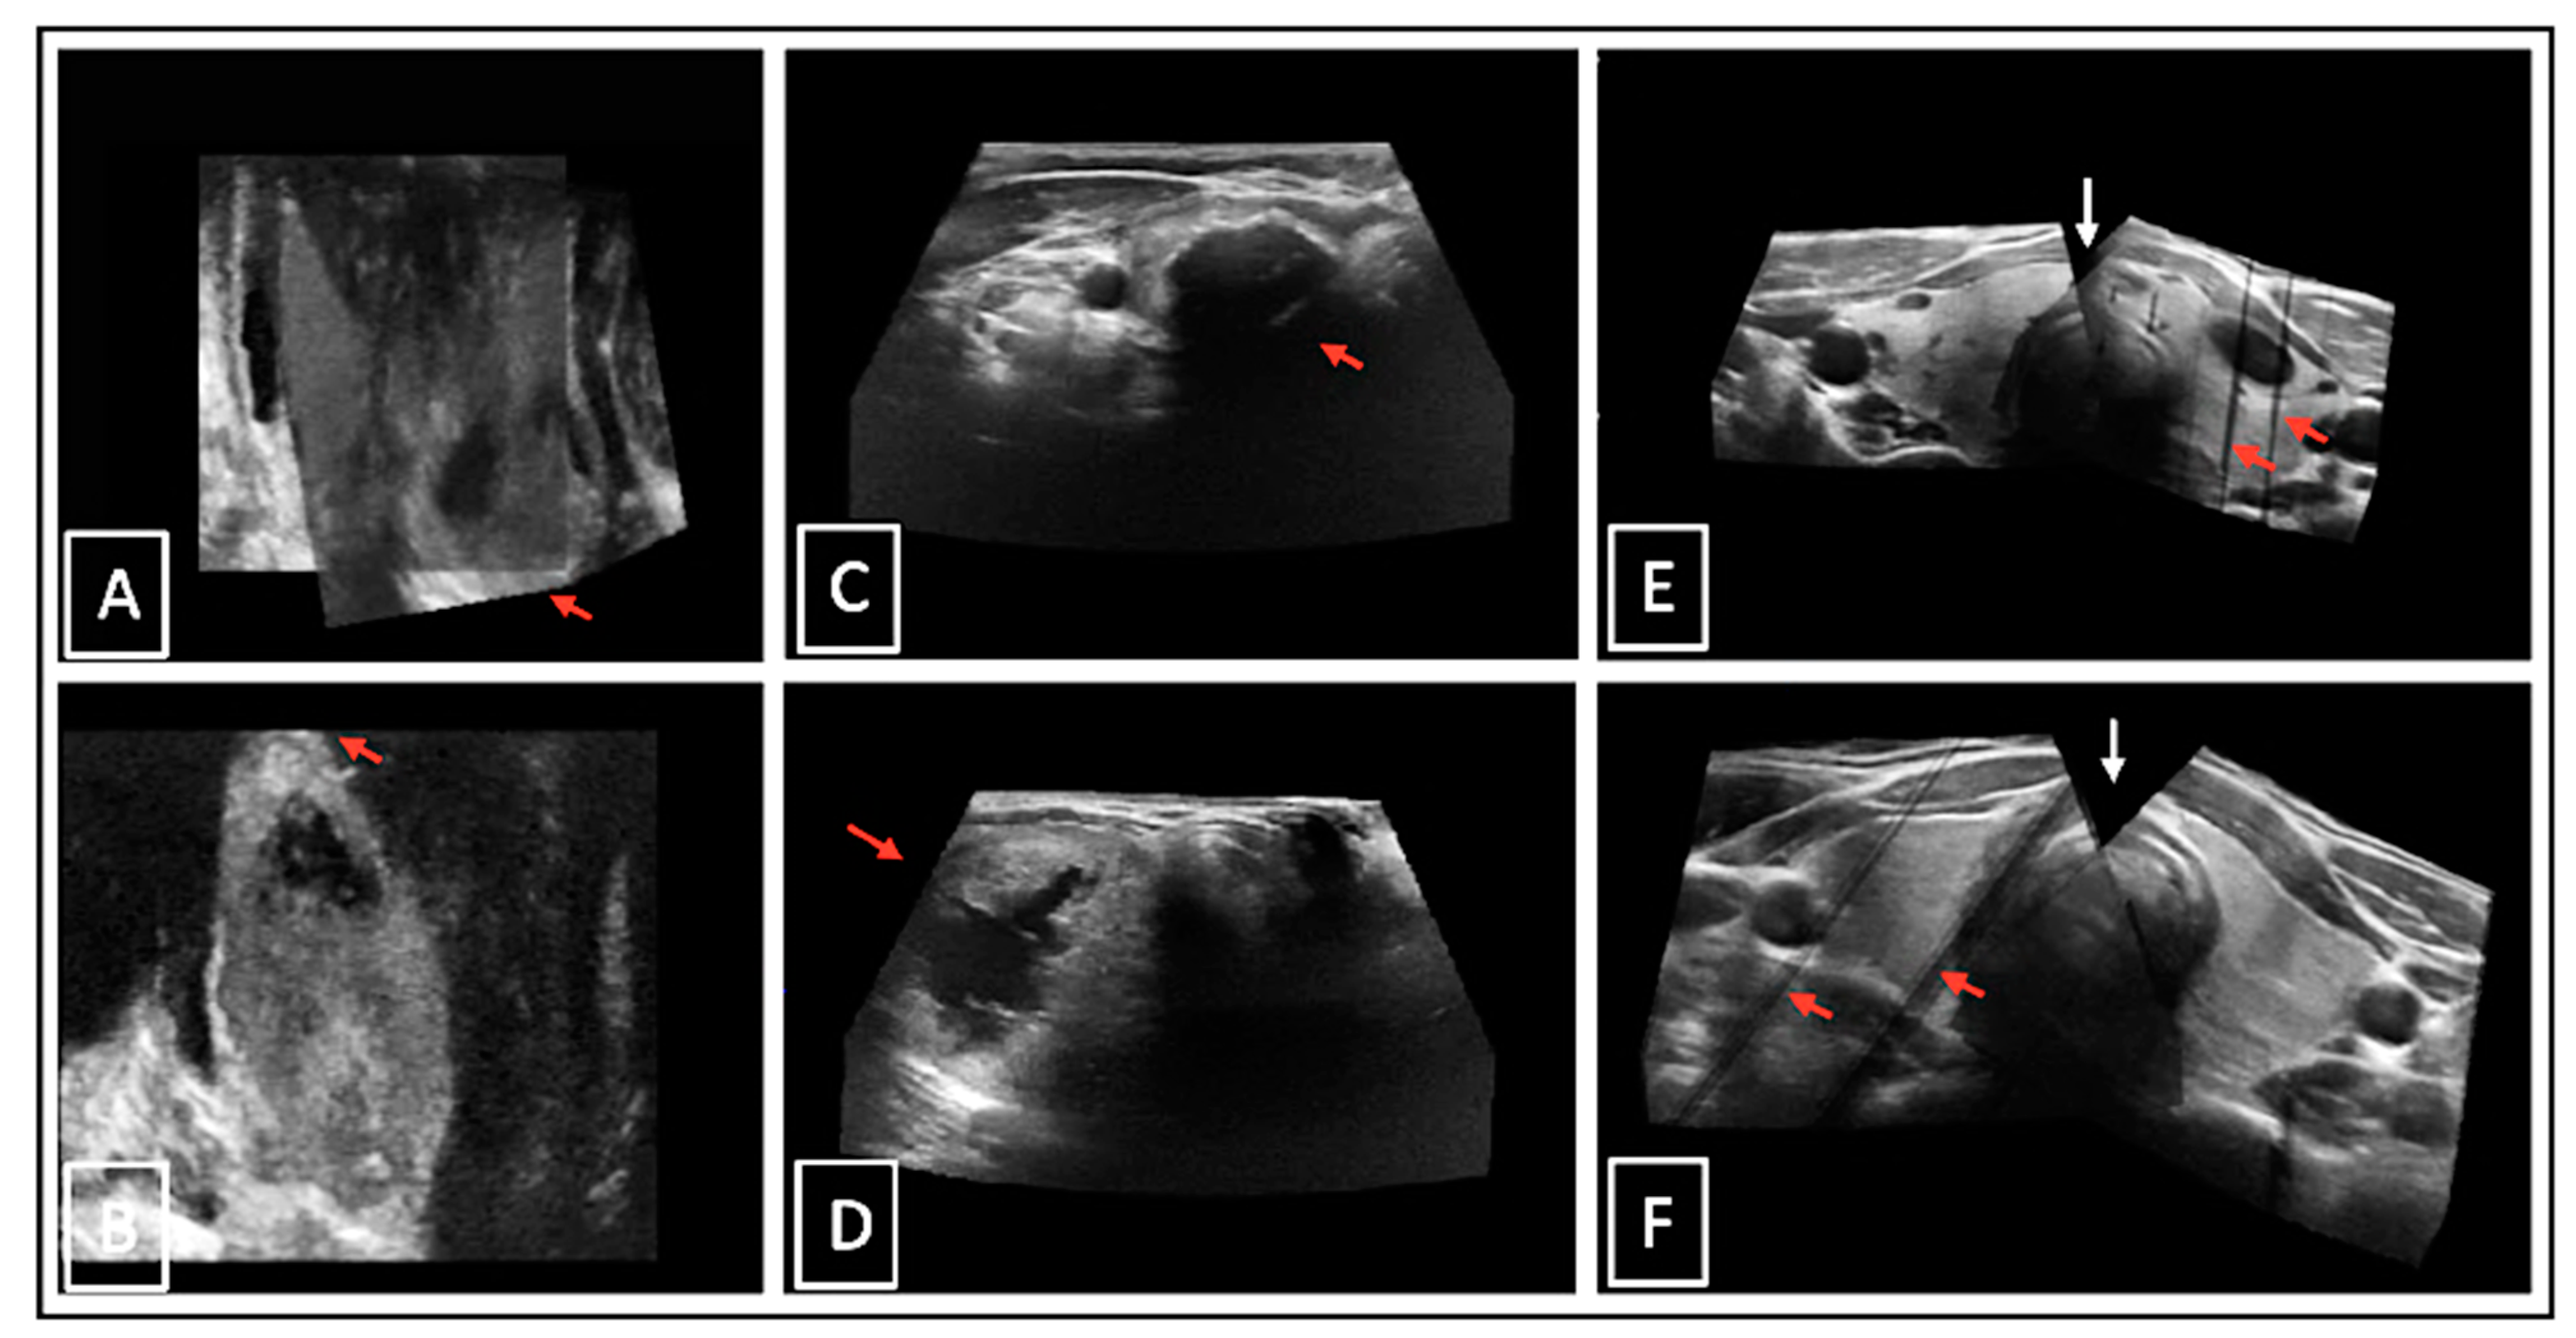

Sensor-navigated 3D-US with the linear matrix array probe ML6-15 (3DsnUS) and mechanically swept 3D-US with the automated motor array 3D convex probe RAB4-8 (3DmsUS) were applicable in all cases. With 3DmsUS, only 21 of the 31 patients were examined due to organizational reasons. However, in a few cases the image quality was not optimal due to artefacts or incompletely captured pols and isthmuses (Figure 7), but still sufficient for diagnostic demands. No examinations needed to be excluded because of poor image quality.

Figure 7.

Examples of suboptimal 3D-US images: incompletely captured thyroid pols on 3DmsUS in coronal plane ((A,B), red arrows); incompletely displayed thyroid tissue due to dorsal acoustic deletions behind calcifications ((C), red arrow) and a large nodule ((D), red arrow) in transverse plane; incompletely displayed isthmus ((E,F), white arrows) and artefacts due to too-fast moved US probe while 3D scan acquisition ((E,F), red arrows).